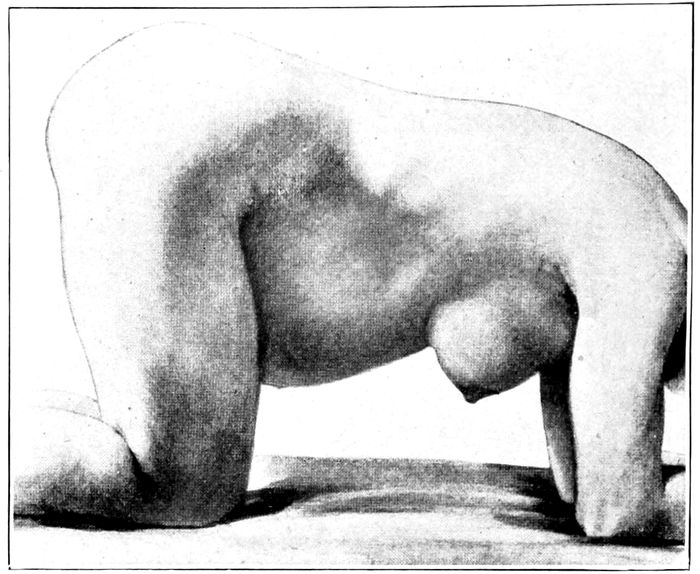

| 100. |

The knee-elbow posture |

236 |

| |

| 101. |

The knee-chest posture |

236 |

| |

| 16102. |

The exaggerated lithotomy position obtained with a sheet sling |

237 |

| |

| 103. |

The improvised Trendelenburg position |

237 |

| |

| 104. |

The dorsal position with stirrups |

238 |

| |

| 105. |

Dorsal position across the bed |

239 |

| |

| 106. |

Flexed dorsal position with feet on the table |

240 |

| |

| 107. |

The Sims position |

241 |